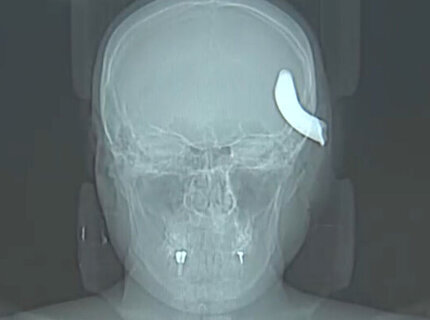

В Петербурге нейрохирурги извлекли из черепа молодого мужчины металлический крюк от буксировочного троса